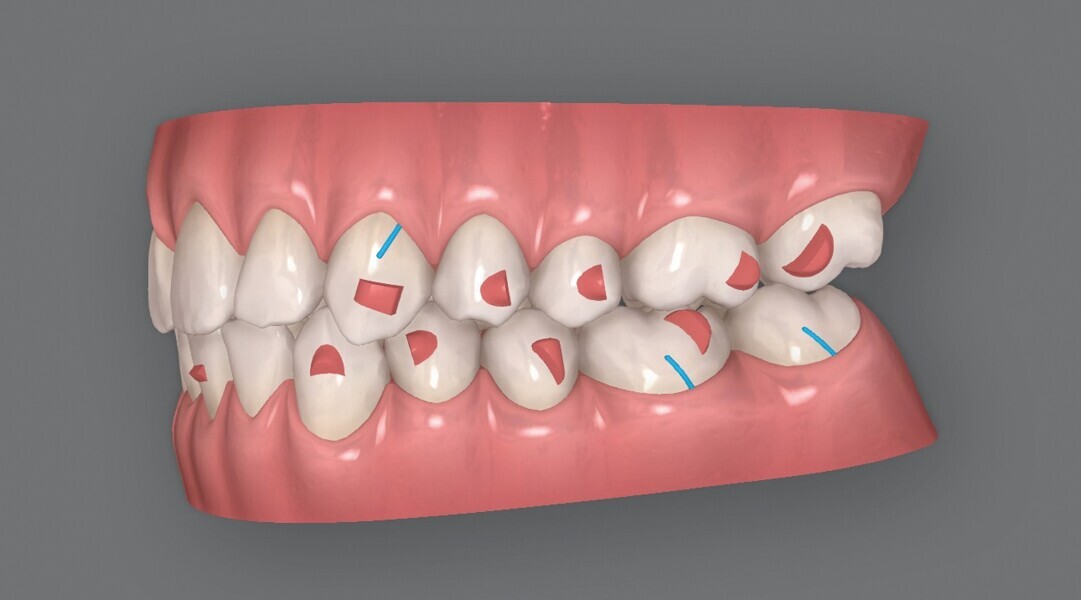

Fig. 4a : Premier résultat prévu par simulation ClinCheck.

Fig. 4b : Premier résultat prévu par simulation ClinCheck.

Fig. 4c : Premier résultat prévu par simulation ClinCheck.

Fig. 4d : Premier résultat prévu par simulation ClinCheck.

Fig. 4e : Premier résultat prévu par simulation ClinCheck.

Le premier plan de traitement par simulation ClinCheck prévoit 53 aligneurs, afin de réaliser une distalisation séquentielle postérieure d’environ 4 mm sur le côté gauche du maxillaire, une expansion de 2 mm par quadrant et un alignement dans la zone antérieure. Il prévoit également une réduction interproximale (RIP) sélective de 0,25 mm sur chaque face des dents de l’arcade mandibulaire, et de 0,10 mm à 0,15 mm pour les dents de l’hémiarcade maxillaire droite (Fig. 4). Une application topique de fluorure est planifiée dans les zones soumises à une RIP après la procédure. Des élastiques de classe II sont utilisés du côté gauche pour faciliter la distalisation. La fréquence de changement des aligneurs est fixée à sept jours et elle sera ramenée à cinq jours par la suite. Un accélérateur de traitement orthodontique par vibrations est utilisé, afin d’augmenter la vitesse et la prédictibilité des mouvements dentaires. Le traitement n’envisage pas l’utilisation d’aligneurs de surcorrection.